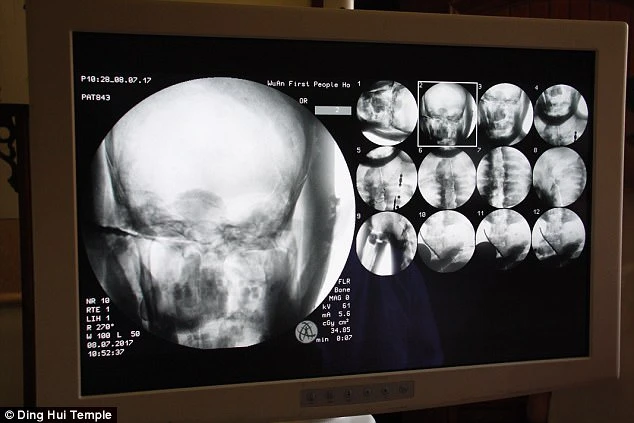

Đại sư Ci Xian được cho là một nhà sư được kính trọng, đã đi từ Ấn Độ sang Trung Quốc vào thời cổ đại để truyền bá Phật giáo. Việc chụp CT đã diễn ra vào ngày 8-7 và được chứng kiến bởi các nhà sư, giới truyền thông và tín đồ Phật giáo. Mọi người đã ngạc nhiên khi các bác sĩ nói Đại sư vẫn còn một bộ xương đầy đủ, và một bộ não hoàn chỉnh.

Tiến sĩ Wu Yongqing nói với Pear Video sau khi quét: "Chúng ta có thể thấy xương của ngài khỏe mạnh như người bình thường. Hàm trên, răng trên, xương sườn, xương sống và tất cả các khớp xương đều hoàn chỉnh. Thật không thể tin được khi nhìn thấy điều đó...".

Bức tượng có một bộ xương, các khớp

và một bộ não hoàn chỉnh